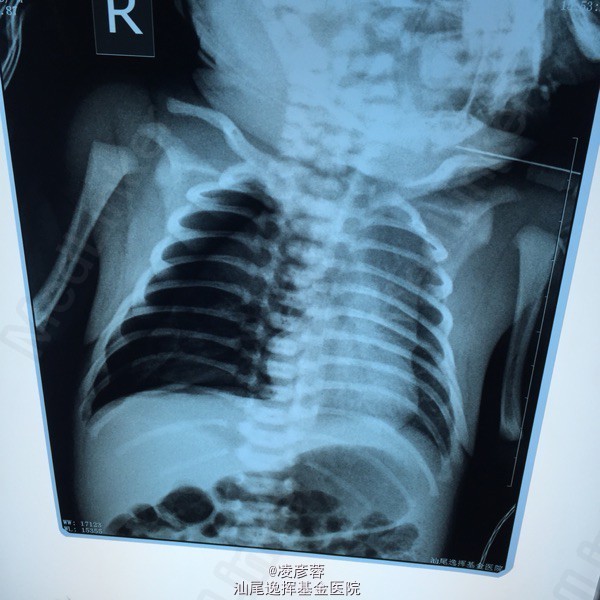

新生儿气胸

出生1天的新生儿,出生情况可,阿氏评分9—10—10;因“呻吟样呼吸1小时”入院。入院诊断考虑:气促查因:新生儿呼吸窘迫综合征 辅查胸片示右侧气胸

新生儿气胸一例